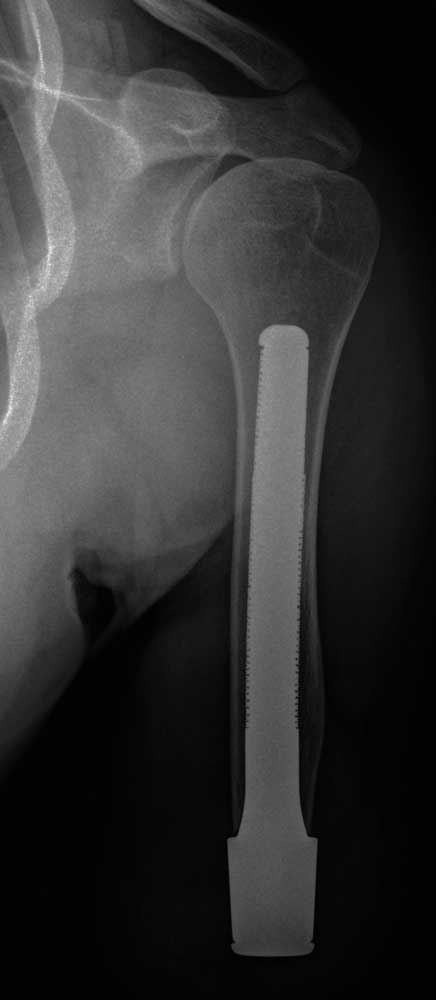

Versorgungsbeispiel transhumeral: Patient B, 29 Jahre

Amputationsgrund: Polytrauma OAAmputation links, US-Amputation rechts

Passteile: Bebionic-Hand, Rotationseinheit, ErgoArm Hybrid, Zweikanalsteuerung mit MyoBock-Elektroden, Silikonhaltebandage zur kontralateralen Seite (nur vor TOPS)

Die Rehabilitation einer traumatischen Oberarmamputation mit konventionellem Schaftsystem gestaltet sich bei kurzen Stümpfen oft schwierig. Die Probleme bestehen in einer nicht zufriedenstellenden Schulterbewegung der amputierten Seite und einer durch die Schulterbandage eingeschränkten kontralateralen Seite.

Patient B wurde im August 2015 mit einem individuellen HTV-Silikonliner mit Velcro-Verschlusssystem und einer HTV-Silikonhaltebandage zur kontralateralen Seite versorgt. Die Versorgung wird myoelektrisch betrieben; somit war die Positionssicherung der Prothese entscheidend für die Ansteuerung. Durch die Kürze des Stumpfes war das Ergebnis aber nur wenig zufriedenstellend. Die Montage der Prothese wurde nach den herkömmlichen Aufbaurichtlinien und unter Berücksichtigung des Eigengewichts der Passteilkomponenten vorgenommen. Das Brückenmodul ist distal mit einer Pyramidenaufnahme versehen, an dem ein Custommade-Adapter befestigt wurde, um die Verbindung zum ErgoArm Hybrid herzustellen. Nach vierwöchigem Tragen wurde festgestellt, dass sich die muskuläre Situation im Schultergürtel des Patienten deutlich verändert hat: Nach deutlicher Atrophie der amputierten Seite findet sich nun eine verbesserte muskuläre Situation. Dies hatte Konsequenzen für den statischen Prothesenaufbau. Die Ellenbogenachse hatte sich durch erhöhte Abduktion im Schulterbereich verändert, wiederum mit Einfluss auf den Custom-made-Adapter und die Passteile. Somit war es notwendig, den Aufbau anzupassen.

Aufbau und Sitz der Prothese wurden in regelmäßigen Abständen überprüft, und nach etwa 3 Monaten konnten keine signifikanten Veränderungen mehr feststellt werden. Somit war es möglich, die kosmetische Verkleidung herzustellen, die mittels Scan und Spiegelung der kontralateralen Seite per 3D-Druck in Polyamid gefertigt wurde. Es wurde jeweils eine Verkleidung für den Unterarm und für den Oberarm gedruckt. Diese sind atmungsaktiv und nachstellbar im Sinne einer statischen Veränderung und einer Volumenänderung. Die Verkleidung für den Oberarm ist mit einem Magnetverschluss versehen und daher zur schnellen und eigenständigen An- und Abnahme geeignet. Heute ist der Patient voll in seinen Alltag integriert und beschreibt eine deutlich bessere Positionierung der Prothese sowie eine sehr leichte Handhabung. Durch die knochengeführten Bewegungen erlangte er eine bessere Krafteinleitung sowie eine osteoperzeptive Fähigkeit. Daher wird eine physiologische Belastungsfähigkeit erreicht (Abb. 13a–c). Die knochengeführten Prothesensysteme sind eine Möglichkeit Patienten, welche nicht oder nur ungenügend mit einer schaftgeführten Prothese rehabilitierbar sind, exoprotetisch zu versorgen. Damit ist eine deutliche Teilhabeverbesserung zu erreichen. Insbesondere für Patienten mit transhumeraler Amputation ist die knochengeführte Prothesenverankerung eine Technologie, mit welcher das Schultergelenk im Bewegungsumfang nicht beeinträchtigt wird und eine sichtbare Verbesserung der Körpersymetrie erreich werden kann.